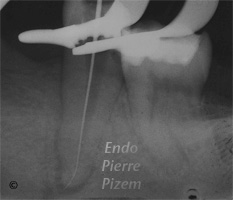

L’apport de l’OPMI PROergo lors du retrait d’un fragment de Lentulo dans le tiers apical du canal mésio vestibulaire

Étude de cas numero: 491047 Image 1: Fragment de